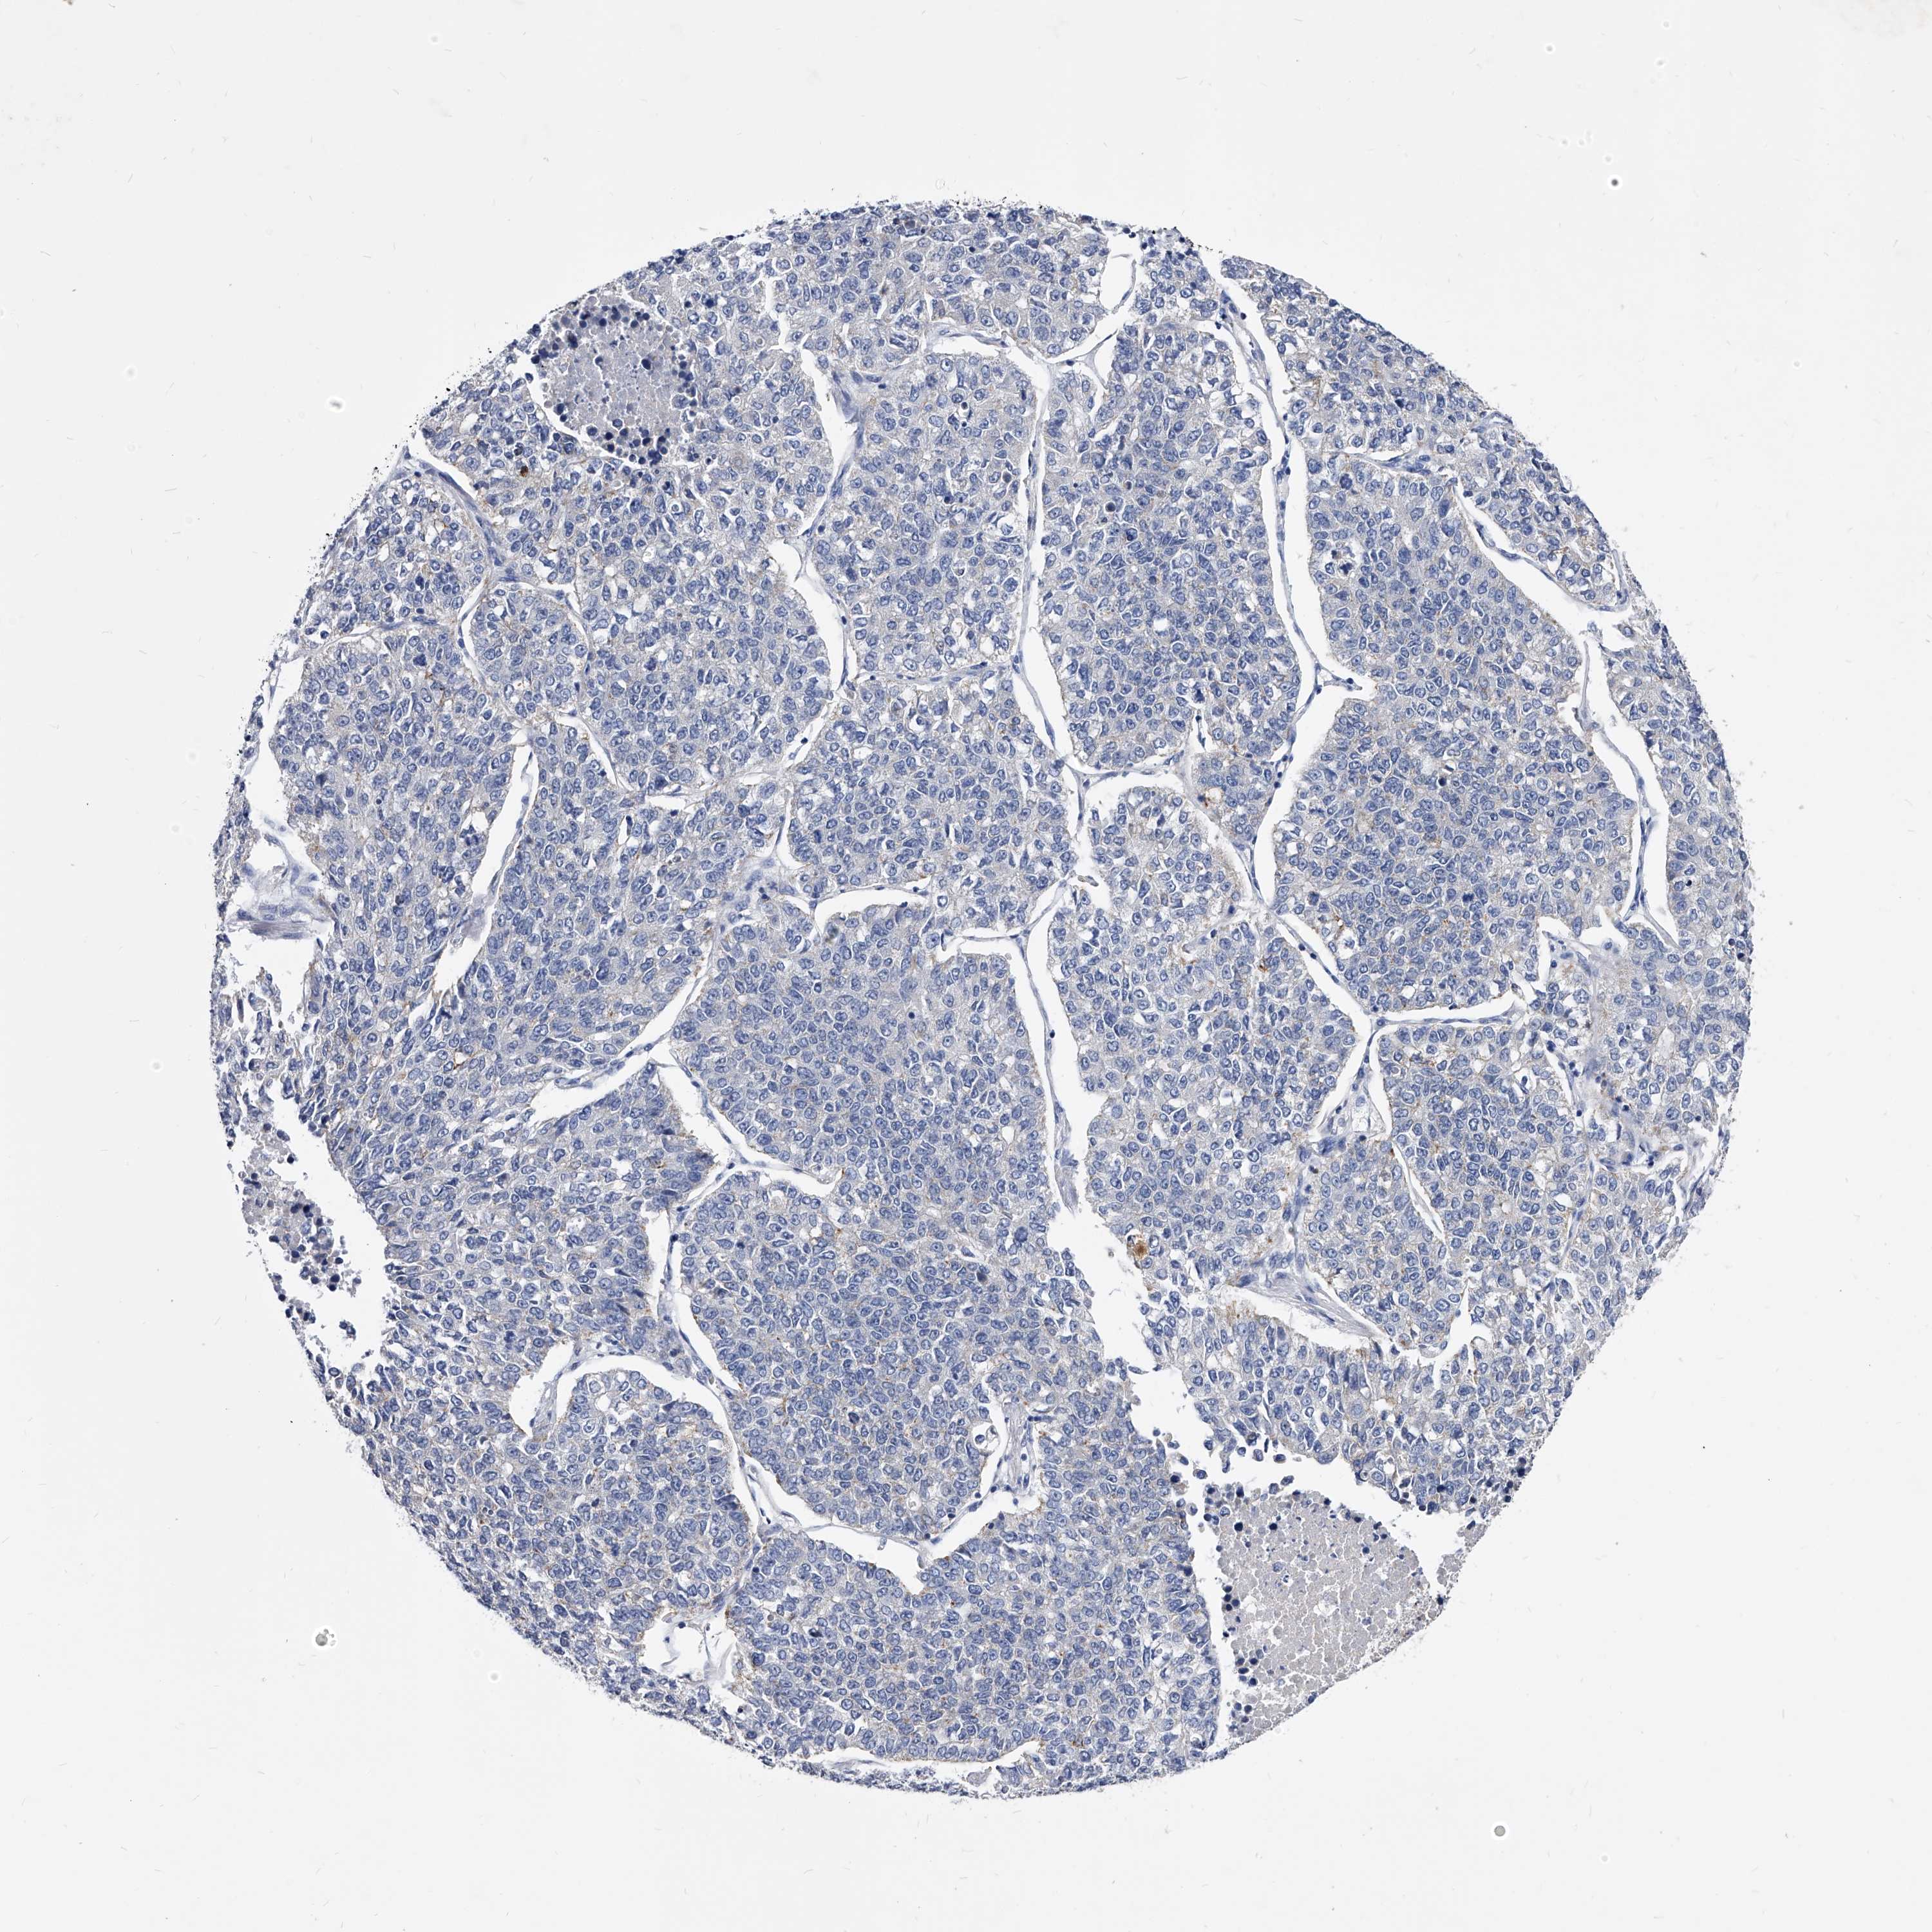

CANCER LUNG CANCER Show tissue menu

Lung cancer

Human cancer

Lung adenocarcinoma

Lung squamous cell carcinoma